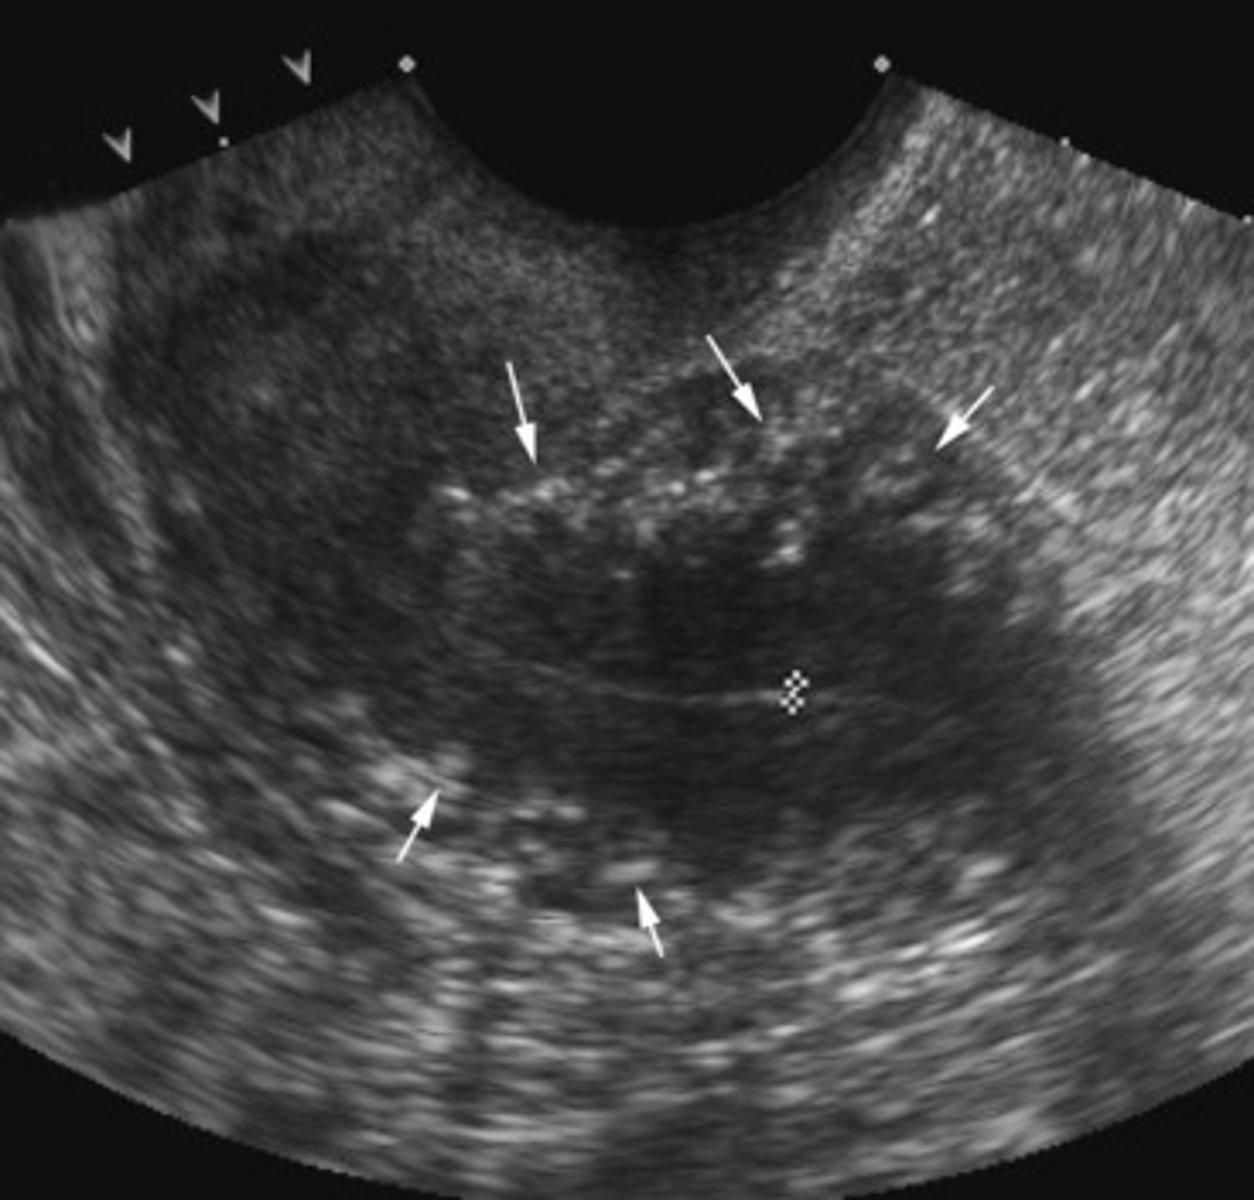

Simple cyst

cyst that has just fluid contents

Complex cyst

cyst which has fluid and solid qualities

Mass

an important change that can occur with or without calcifications; it can represent a cyst, non cancerous tumor, or breast cancer